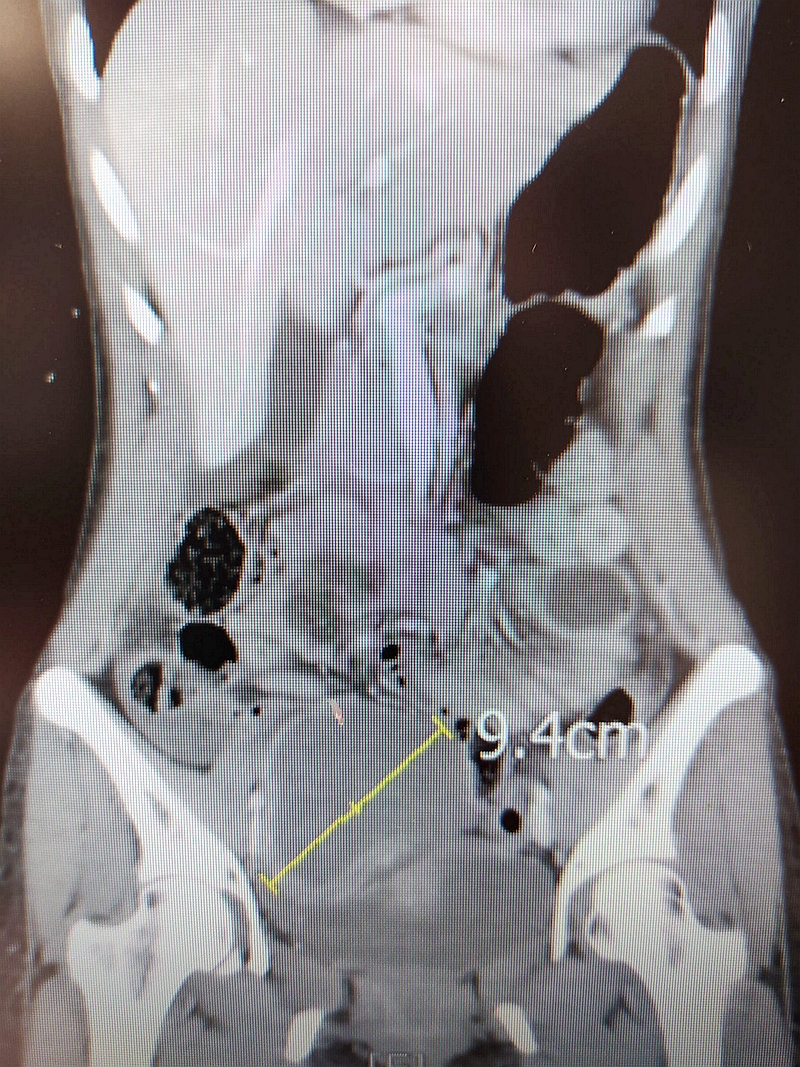

婦人表示,往常經期都沒有特別感覺,今年初起卻每次經期都疼痛不已,在他院就醫服藥幾個月後,右腹竟明顯突出,五月底更劇痛到全身冷汗,直接被送到急診就醫。婦產科醫師黃閔暄從電腦斷層影像發現,劇痛病因來自右側卵巢巧克力囊腫破裂,引發急性腹膜炎,屬於不能再等的急症。即使婦人確診感染新冠肺炎病毒,仍緊急安排病人進入負壓隔離病房,醫療團隊全副武裝在負壓隔離手術室開刀,順利用腹腔鏡摘除形狀有如一顆大蘋果的10公分病灶。